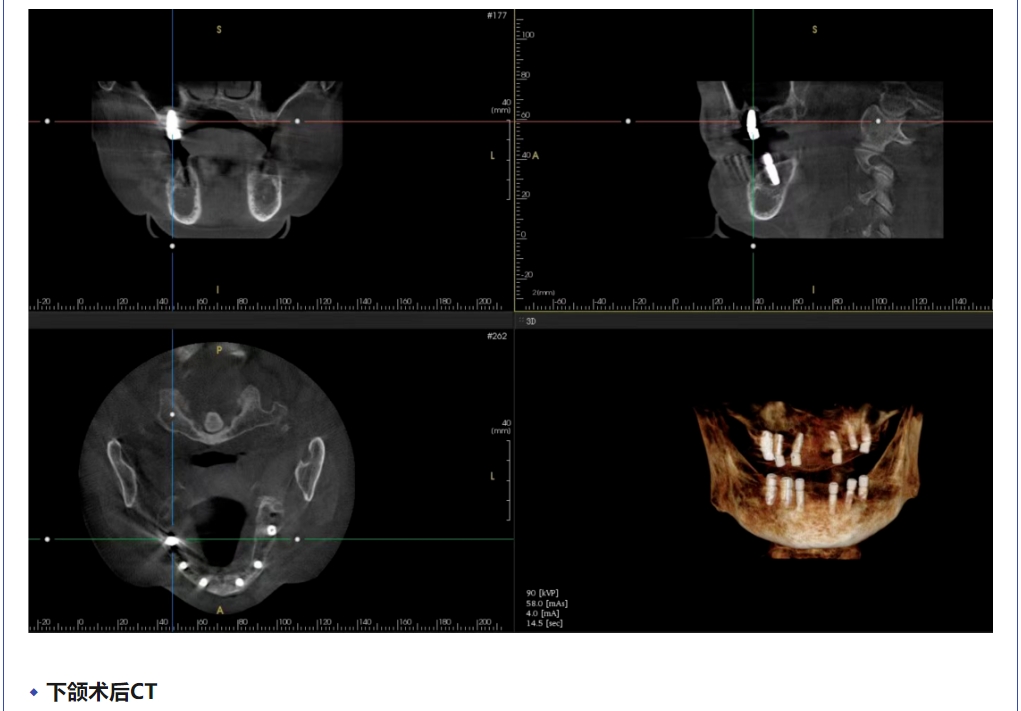

病例分享 | 全口即刻负重一例